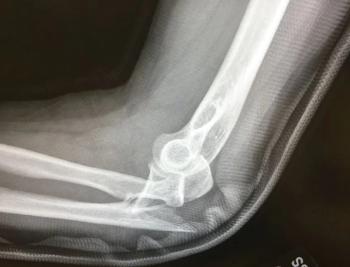

A 66-y/o man presents with worsening generalized headache x2 days plus chills and dry cough. Initial concerns: encephalitis, influenza, URI, pneumonia? Your Dx?